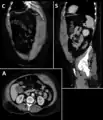

A rectus sheath hematoma is an accumulation of blood in the sheath of the rectus abdominis muscle. It causes abdominal pain with or without a mass.